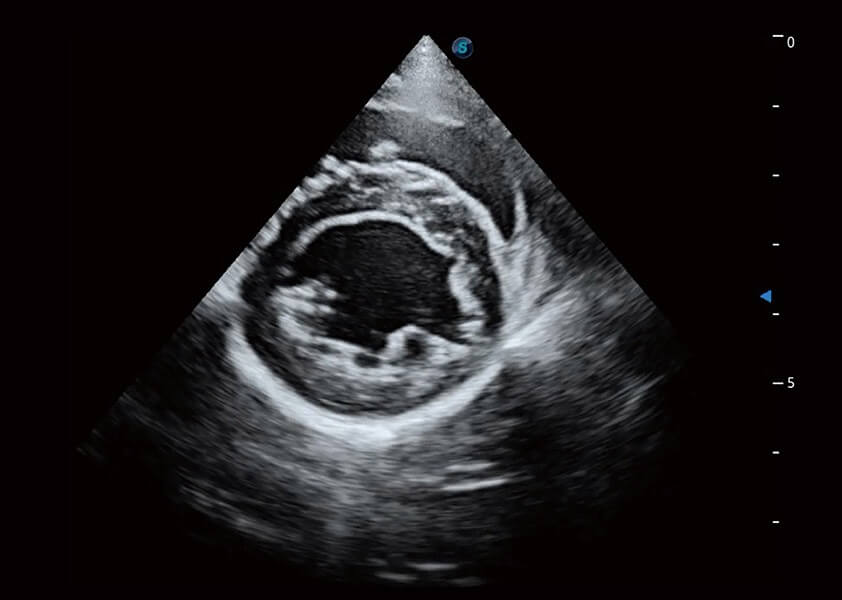

(犬)四腔心血流

(犬)乳头肌短轴